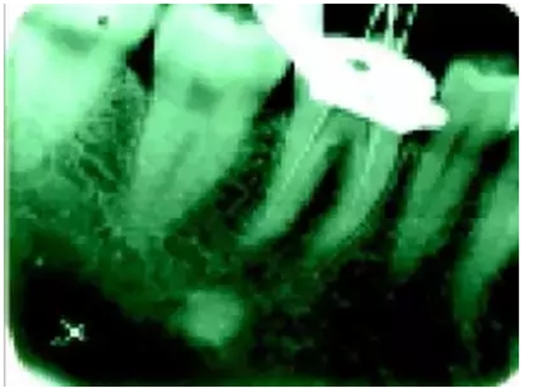

1)尋找遺漏根管

2)根管系統(tǒng)的解剖形態(tài)是極其復(fù)雜的。牙髓病學(xué)教材中常常提到磨牙有三個(gè)根管,前磨牙兩個(gè)根管,前牙一個(gè)根管。實(shí)際上,根管系統(tǒng)并不是如此可預(yù)知的,而是常常存在許多解剖變異。根管系統(tǒng)的解剖形態(tài)學(xué)研究發(fā)現(xiàn):幾乎50%磨牙中(上頜和下頜)有第四根管存在,30%以上的前磨牙有第三根管,接近25%的前牙有雙根管。

在傳統(tǒng)的根管治療中,開髓后往往只是依靠術(shù)者的視覺和經(jīng)驗(yàn)去尋找根管,所以常常存在遺漏根管的可能,從而導(dǎo)致根管治療的失敗。研究發(fā)現(xiàn),X線片上顯示根管充填滿意的患牙仍有癥狀的主要原因是有遺漏的根管未治療。

手術(shù)顯微鏡是用于尋找隱藏或遺漏的根管最重要的工具。因?yàn)槭中g(shù)顯微鏡能夠幫助醫(yī)生觀察到肉眼或普通放大鏡無法分辨的根管口和微小病損。在手術(shù)顯微鏡下,利用高倍數(shù)(16~24倍)的放大作用以及理想的照明條件,仔細(xì)檢查患牙的髓室底,許多細(xì)微的解剖結(jié)構(gòu)能容易被發(fā)現(xiàn)。